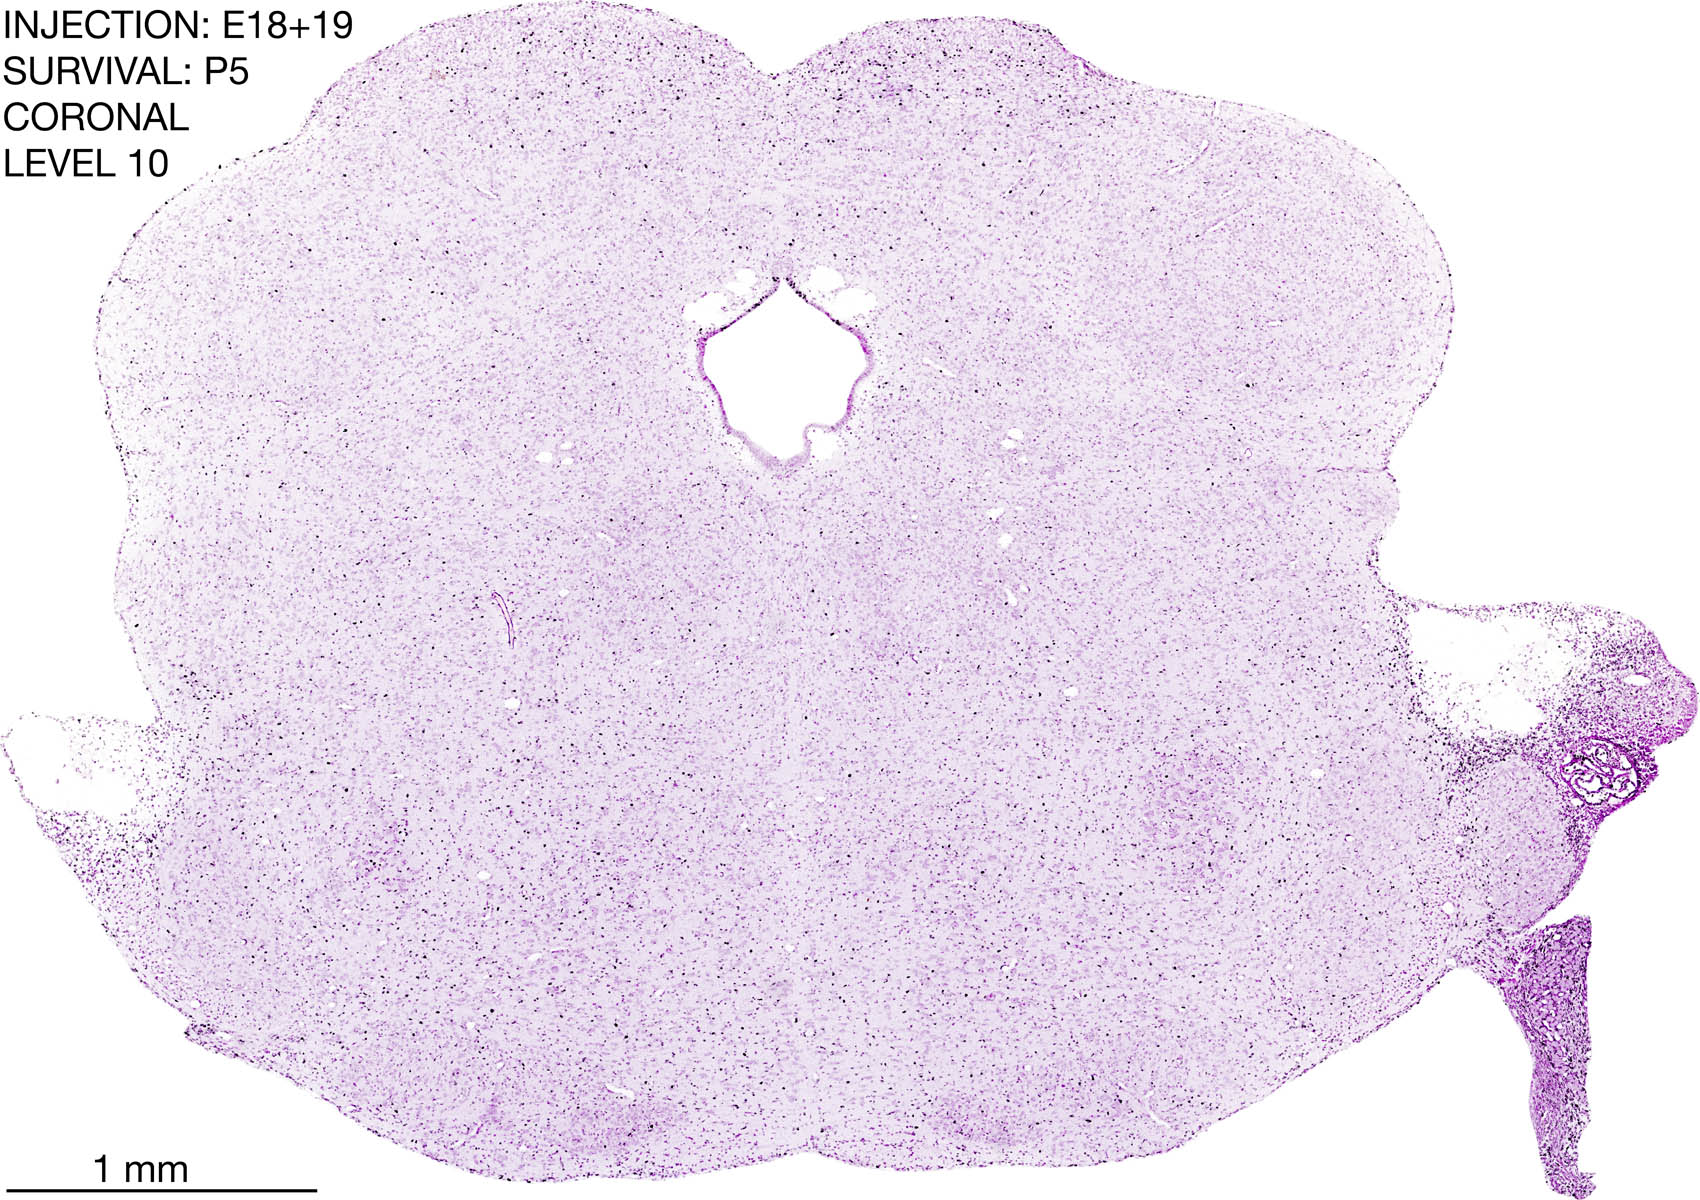

The images below are from the brain of a rat that was exposed to tritiated thymidine on E18+19 and survived to P5. Download: Large | High Res Download: Large | High Res Download: Large | High Res Download: Large | High Res Download: Large | High Res Download: Large | High Res Download: Large | High Res Download: Large | High Res Download: Large | High Res Download: Large | High Res Download: Large | High Res Download: Large | High Res Download: Large | High Res Download: Large | High Res Download: Large | High Res Download: Large | High Res Download: Large | High Res Download: Large | High Res Download: Large | High Res Download: Large | High Res Download: Large | High Res Download: Large | High Res Download: Large | High Res Download: Large | High Res